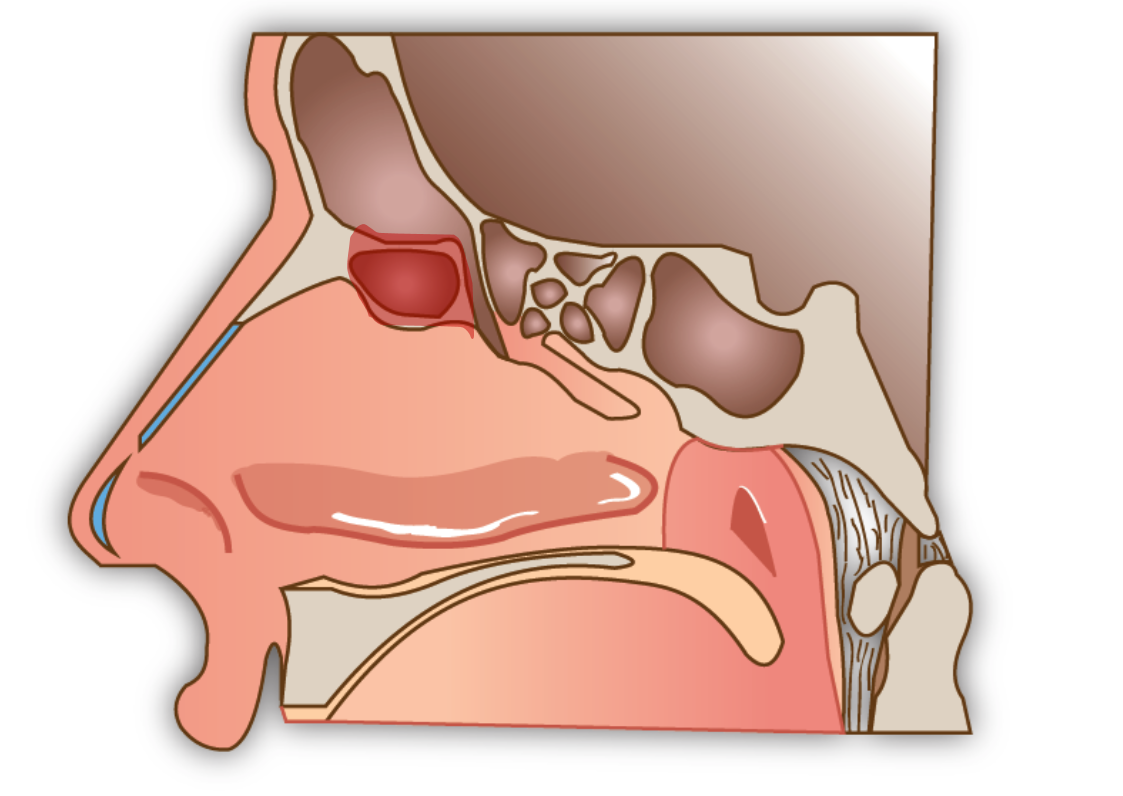

Votre ORL après vous avoir interrogé sur vos symptômes et leurs fréquence, examinera vos sinus. Pour cela il utilisera un nasofibroscope, c’est à dire une caméra flexible qu’il passera à travers vos narines pour regarder vos fosses nasales voire vos sinus. Il recherchera des écoulements purulent pouvant provenir du sinus frontal (en cas de sinusite), voire des tumeurs ce qui est beaucoup plus rare.

Examen clinique